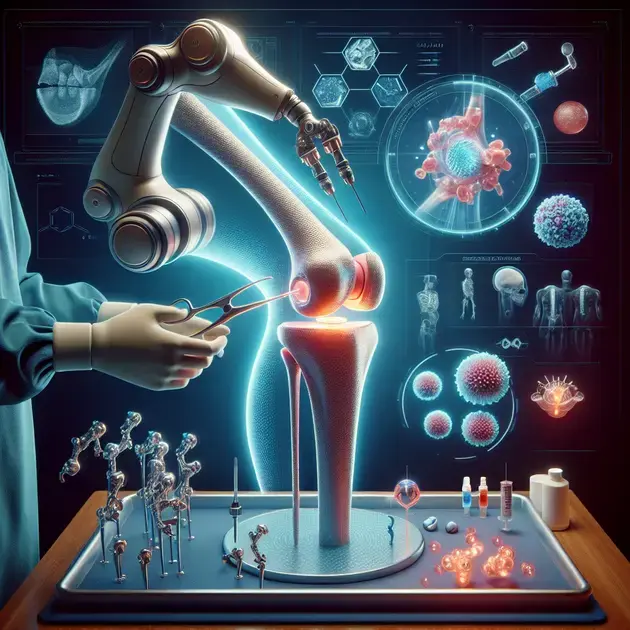

Understanding total knee replacement surgery is essential for those considering the procedure. This surgery is typically recommended for individuals with severe knee arthritis or injuries that have not responded to conservative treatments. Total knee replacement involves removing damaged cartilage and bone from the knee joint and replacing it with an artificial joint made of metal and plastic components.

To gain a better understanding of total knee replacement surgery, educational videos and apps can be useful resources. Platforms like OrthoInfo provide interactive tools and videos that explain the surgical process step-by-step, helping patients visualize what to expect before, during, and after the surgery.